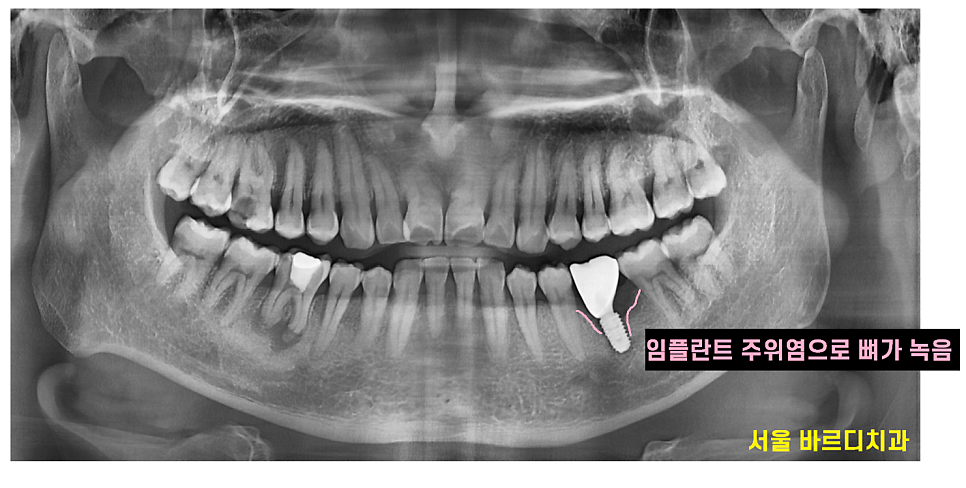

임플란트 주위염이 뭔가요~?

잇몸 염증과 증상이 비슷합니다.

임플란트 주변 잇몸이 붓고 피가 나고

심한 경우 뼈까지 녹일 수 있습니다.

그렇게 되면 심었던 임플란트도 제거해야하죠ㅠㅠ

잇몸 뼈가 녹은거라 눈에는 안보인답니다~